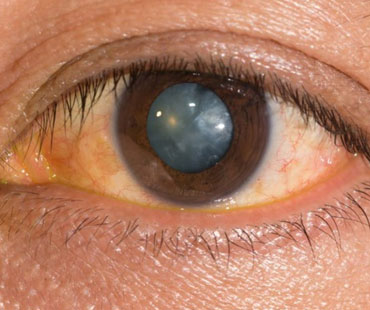

IDR EYE CARE is an eye care facility provider. We specialise in all kind of Cataract, glaucoma, retinal diseases, paediatric ophthalmology, refractive surgeries and more.